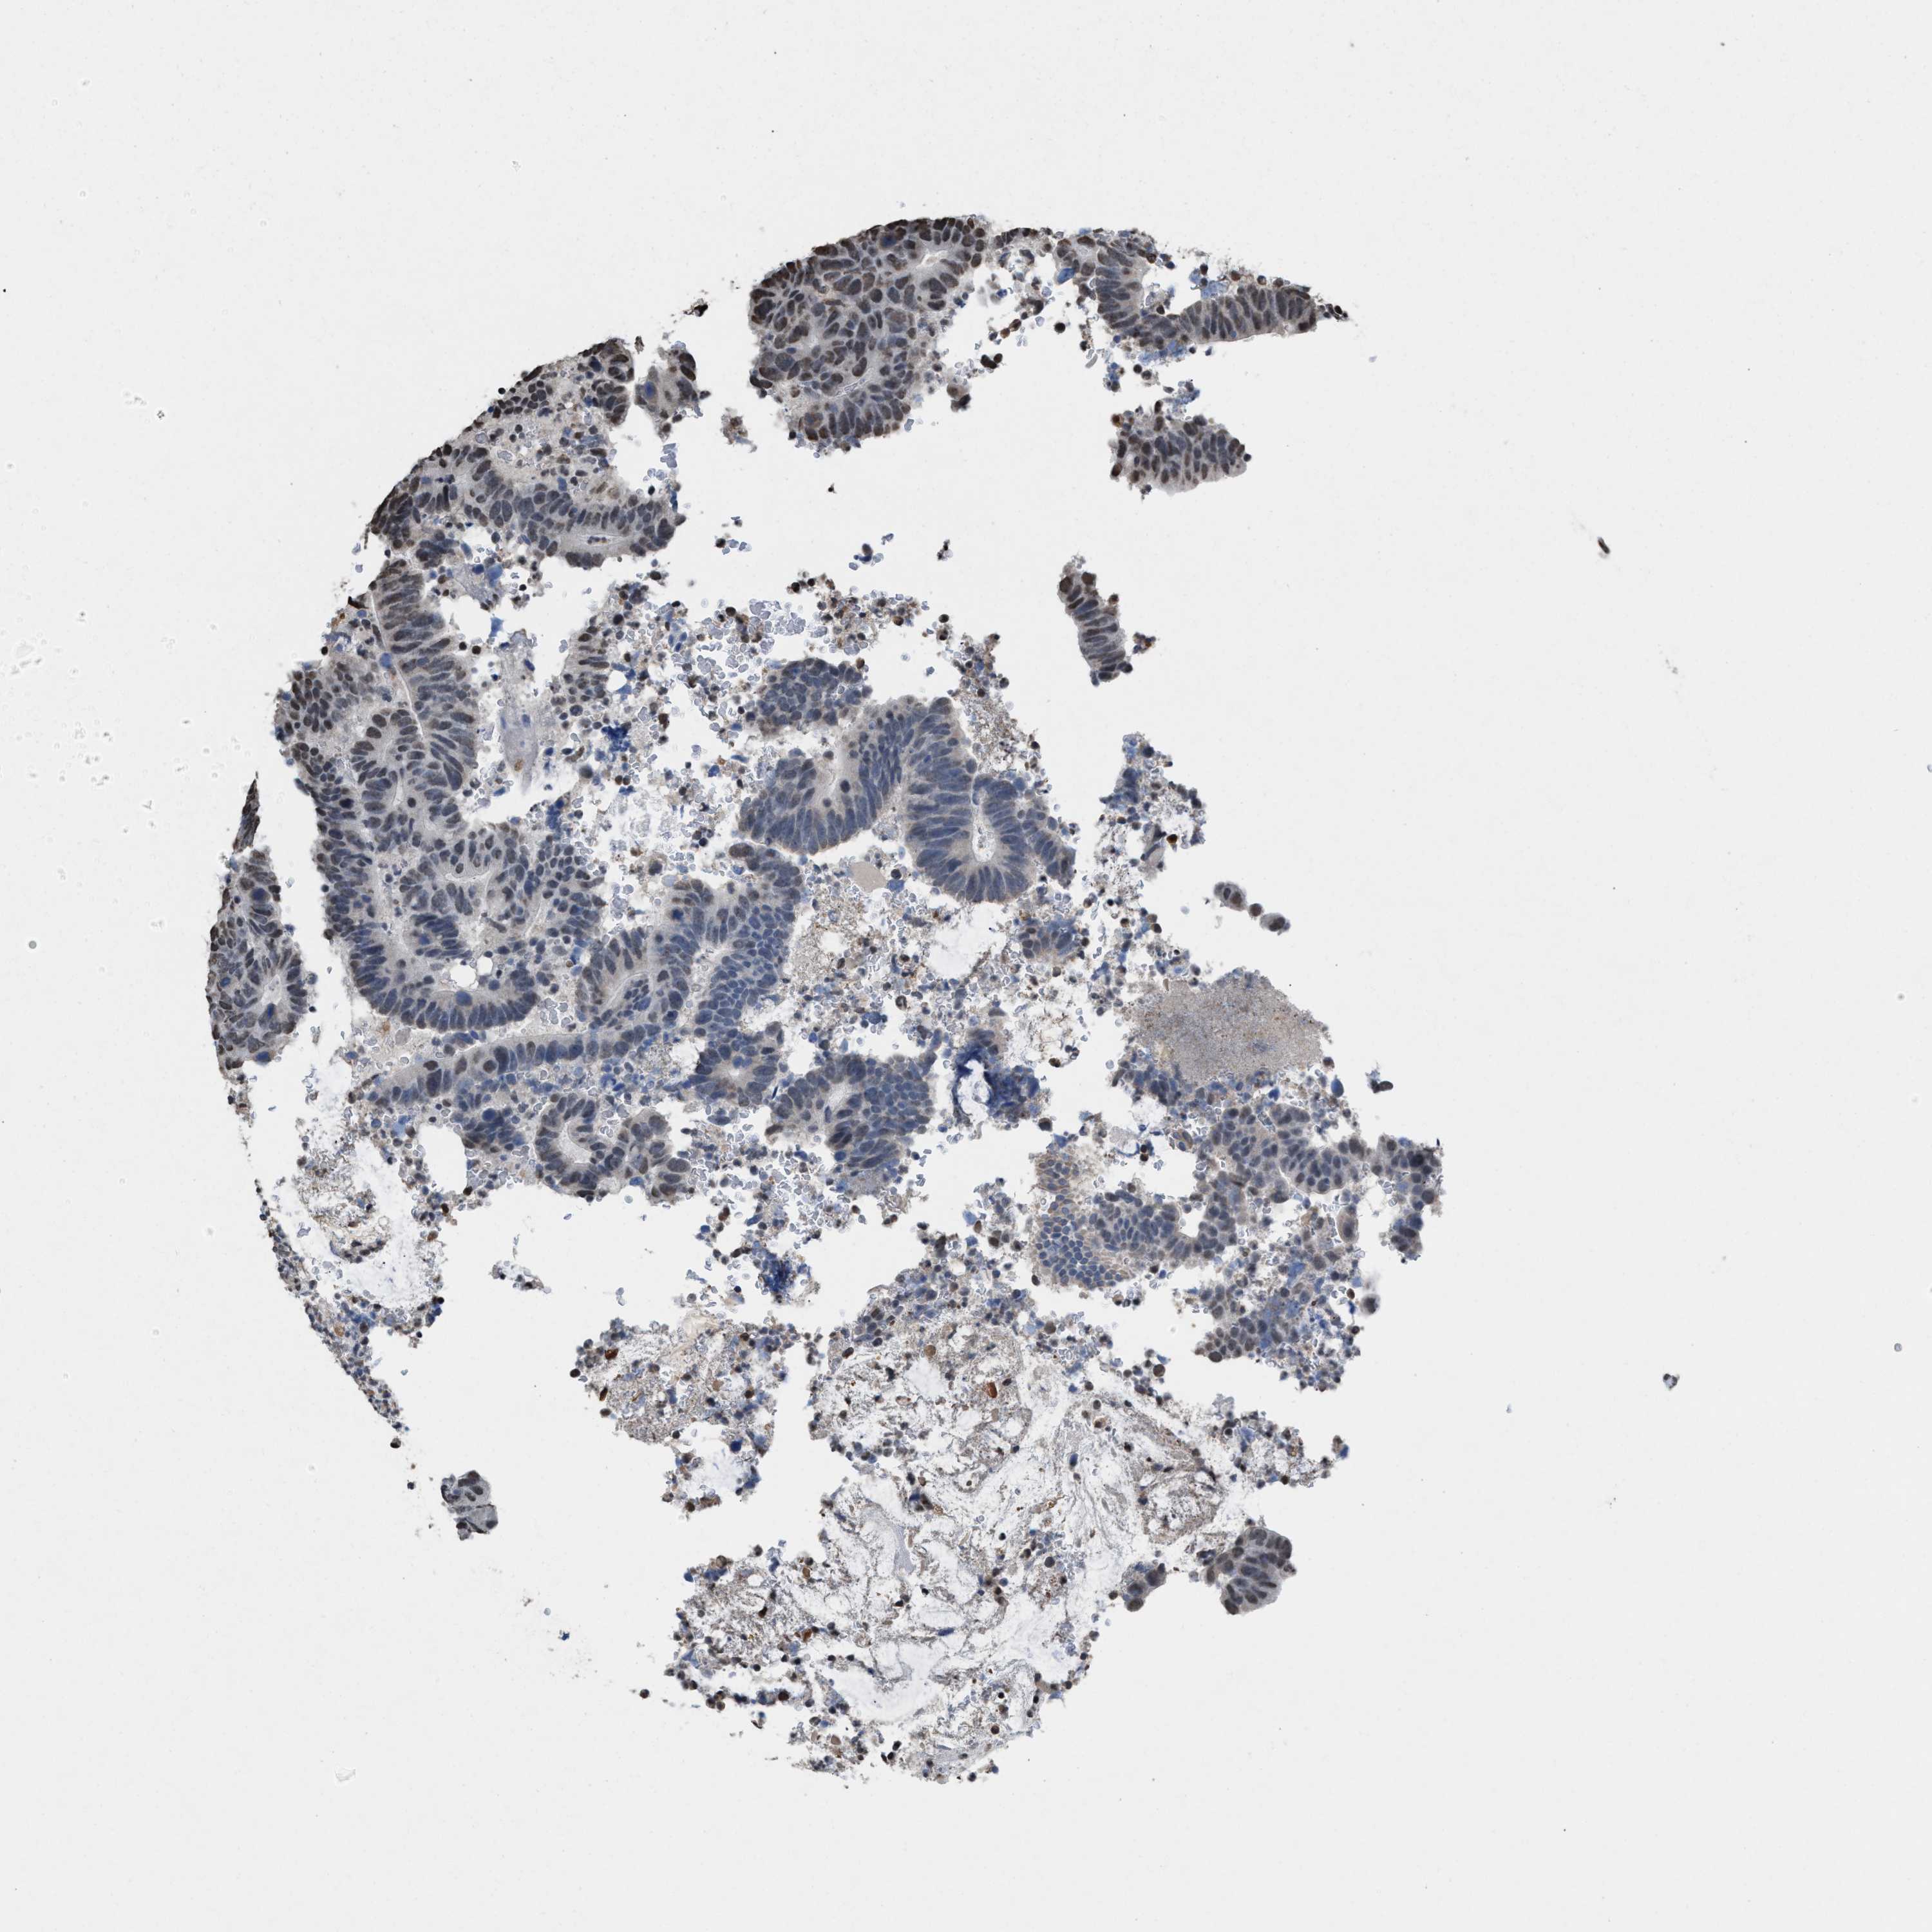

ANTIBODIES

AND

VALIDATION